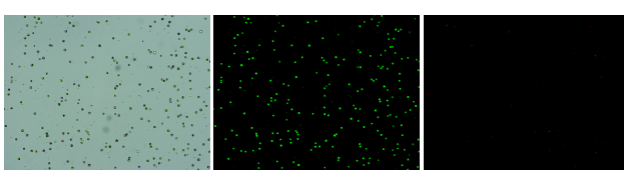

肝臟是人體代謝和解讀的器官,在體內(nèi)發(fā)揮氧化、儲(chǔ)存肝糖、合成分泌性蛋白合成等,肝臟也制造消化系統(tǒng)中之膽汁,人肝約有25億個(gè)肝細(xì)胞。但是解離肝臟組織懸液并不簡單,首先,肝臟代謝旺盛,離體后肝細(xì)胞無法進(jìn)行正常的有氧糖酵解,細(xì)胞活力會(huì)迅速下降,另外,肝細(xì)胞的線粒體很多,每個(gè)細(xì)胞大約有1000個(gè)左右,遍布于胞質(zhì)內(nèi)。因此,很難得到符合單細(xì)胞測序要求的單細(xì)胞懸液。百邁客生物在肝臟組織單細(xì)胞懸液制備方面有豐度的實(shí)操經(jīng)驗(yàn),開發(fā)了獨(dú)有的解離體系,下面來看實(shí)驗(yàn)結(jié)果:

實(shí)驗(yàn)結(jié)果

人肝癌樣本,懸液背景干凈,活性91.69%,結(jié)團(tuán)率6%